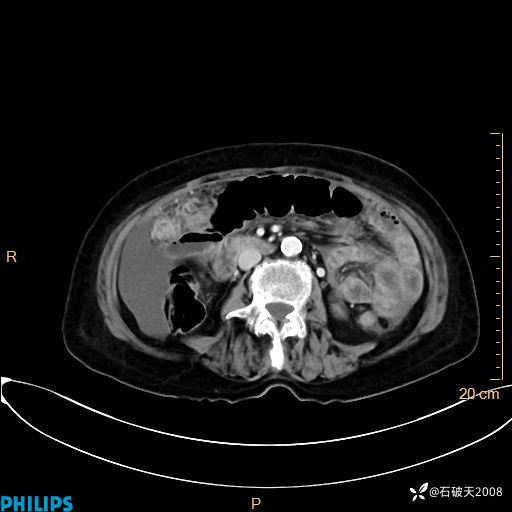

平扫